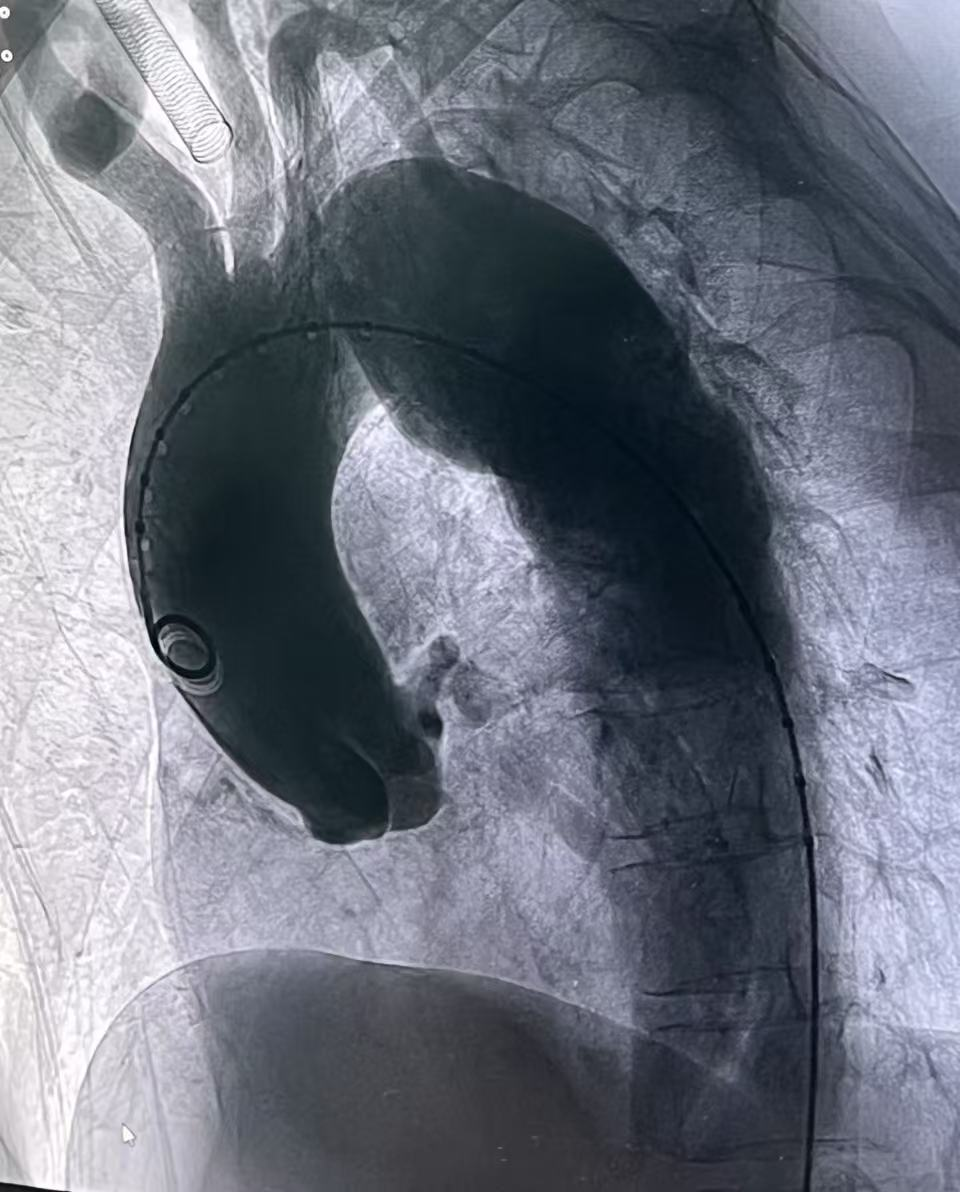

从右侧股动脉入路,使用超滑导丝进入真腔,置入金标猪尾导管造影,再次造影明确夹层真腔位置、形态,可见腹主动脉及降主动脉真腔处多处严重狭窄受压,假腔呈瘤样扩张并累及左侧锁骨下动脉。

术后造影显示,主动脉支架定位精准,三分支支架内血流通畅,夹层内仅有少量膜渗情况。从手术即刻效果来看,该治疗方案达到了预期目标,有效修复了主动脉夹层,恢复了血管的正常解剖结构和血流动力学状态。